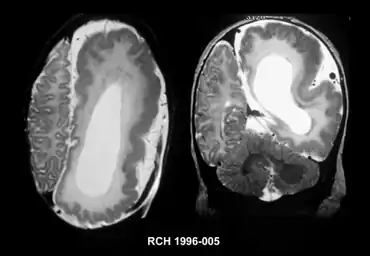

Hemimegalencephaly

| Left-sided hemimegalencephaly in a person with neurofibromatosis[1] | |

Hemimegalencephaly (HME), or unilateral megalencephaly, is a rare congenital disorder affecting all or a part of a cerebral hemisphere.[2] It causes severe seizures, which are often frequent and hard to control. A minority might have seizure control with medicines, but most will need removal or disconnection of the affected hemisphere as the best chance. Uncontrolled, they often cause progressive intellectual disability and brain damage and stop development.[3]

It should be suspected in infants or children with intractable, frequent seizures.[4] On a CT scan, the affected part is distorted and enlarged.[9] It can be diagnosed prenatally, but a lot of cases go undiagnosed until seizures begin. Ultrasound can display asymmetrical brain hemispheres.[5]